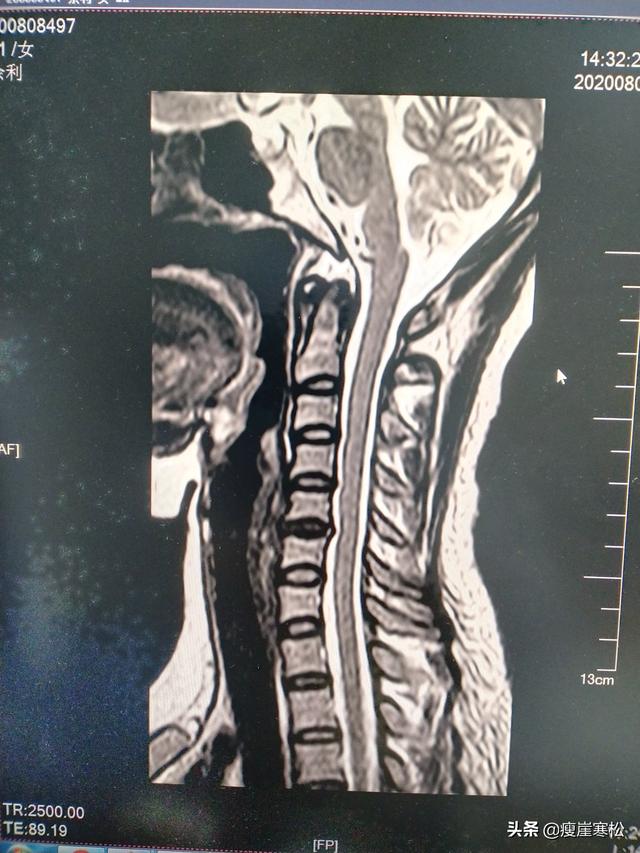

6、早期の頚椎症、首や肩の痛み、ただ頚椎の歪み、椎間板MRIで生理的湾曲の直進が見つかっただけで、他に異常がない場合、脳卒中のリスクがあることを示唆する。

4、頚椎症が椎間板の末端まで深刻な変性を起こしている場合。椎間板ヘルニア、あるいは脱出して、硬膜嚢を圧迫しているように見えるだけでなく、深刻な症状の神経根、手のしびれ、めまいなどが続いていることを示唆している、あなたの脳は、血液供給が深刻に不足している可能性があり、脳卒中は遠くないあなたの側面に表示されます。

頚椎症:これはまた冠状動脈性心臓病とは異なり、頚椎症は脳梗塞の一般的な原因であり、頚椎は特殊な位置にあり、心臓から脳への血液供給に必要なルートであり、頚椎が病気になると、頚動脈や頭蓋領域の血管の痙攣や収縮を引き起こし、正常な血液の流れに影響を及ぼし、脳梗塞が発生する。